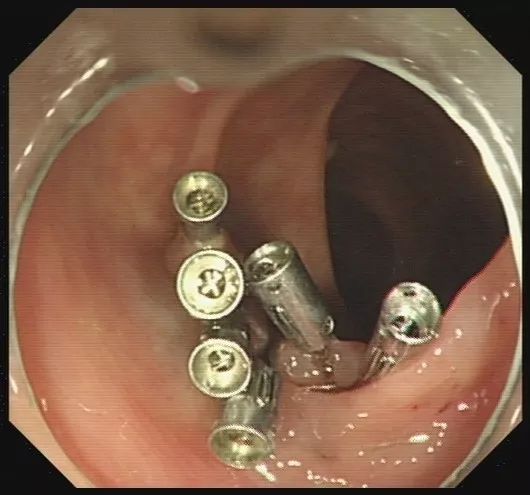

步骤六:为防止创面迟发性出血,可以使用金属夹子夹闭创面。本图为夹子在创面旁打开。

图片

步骤七:金属夹子于创面处夹闭。